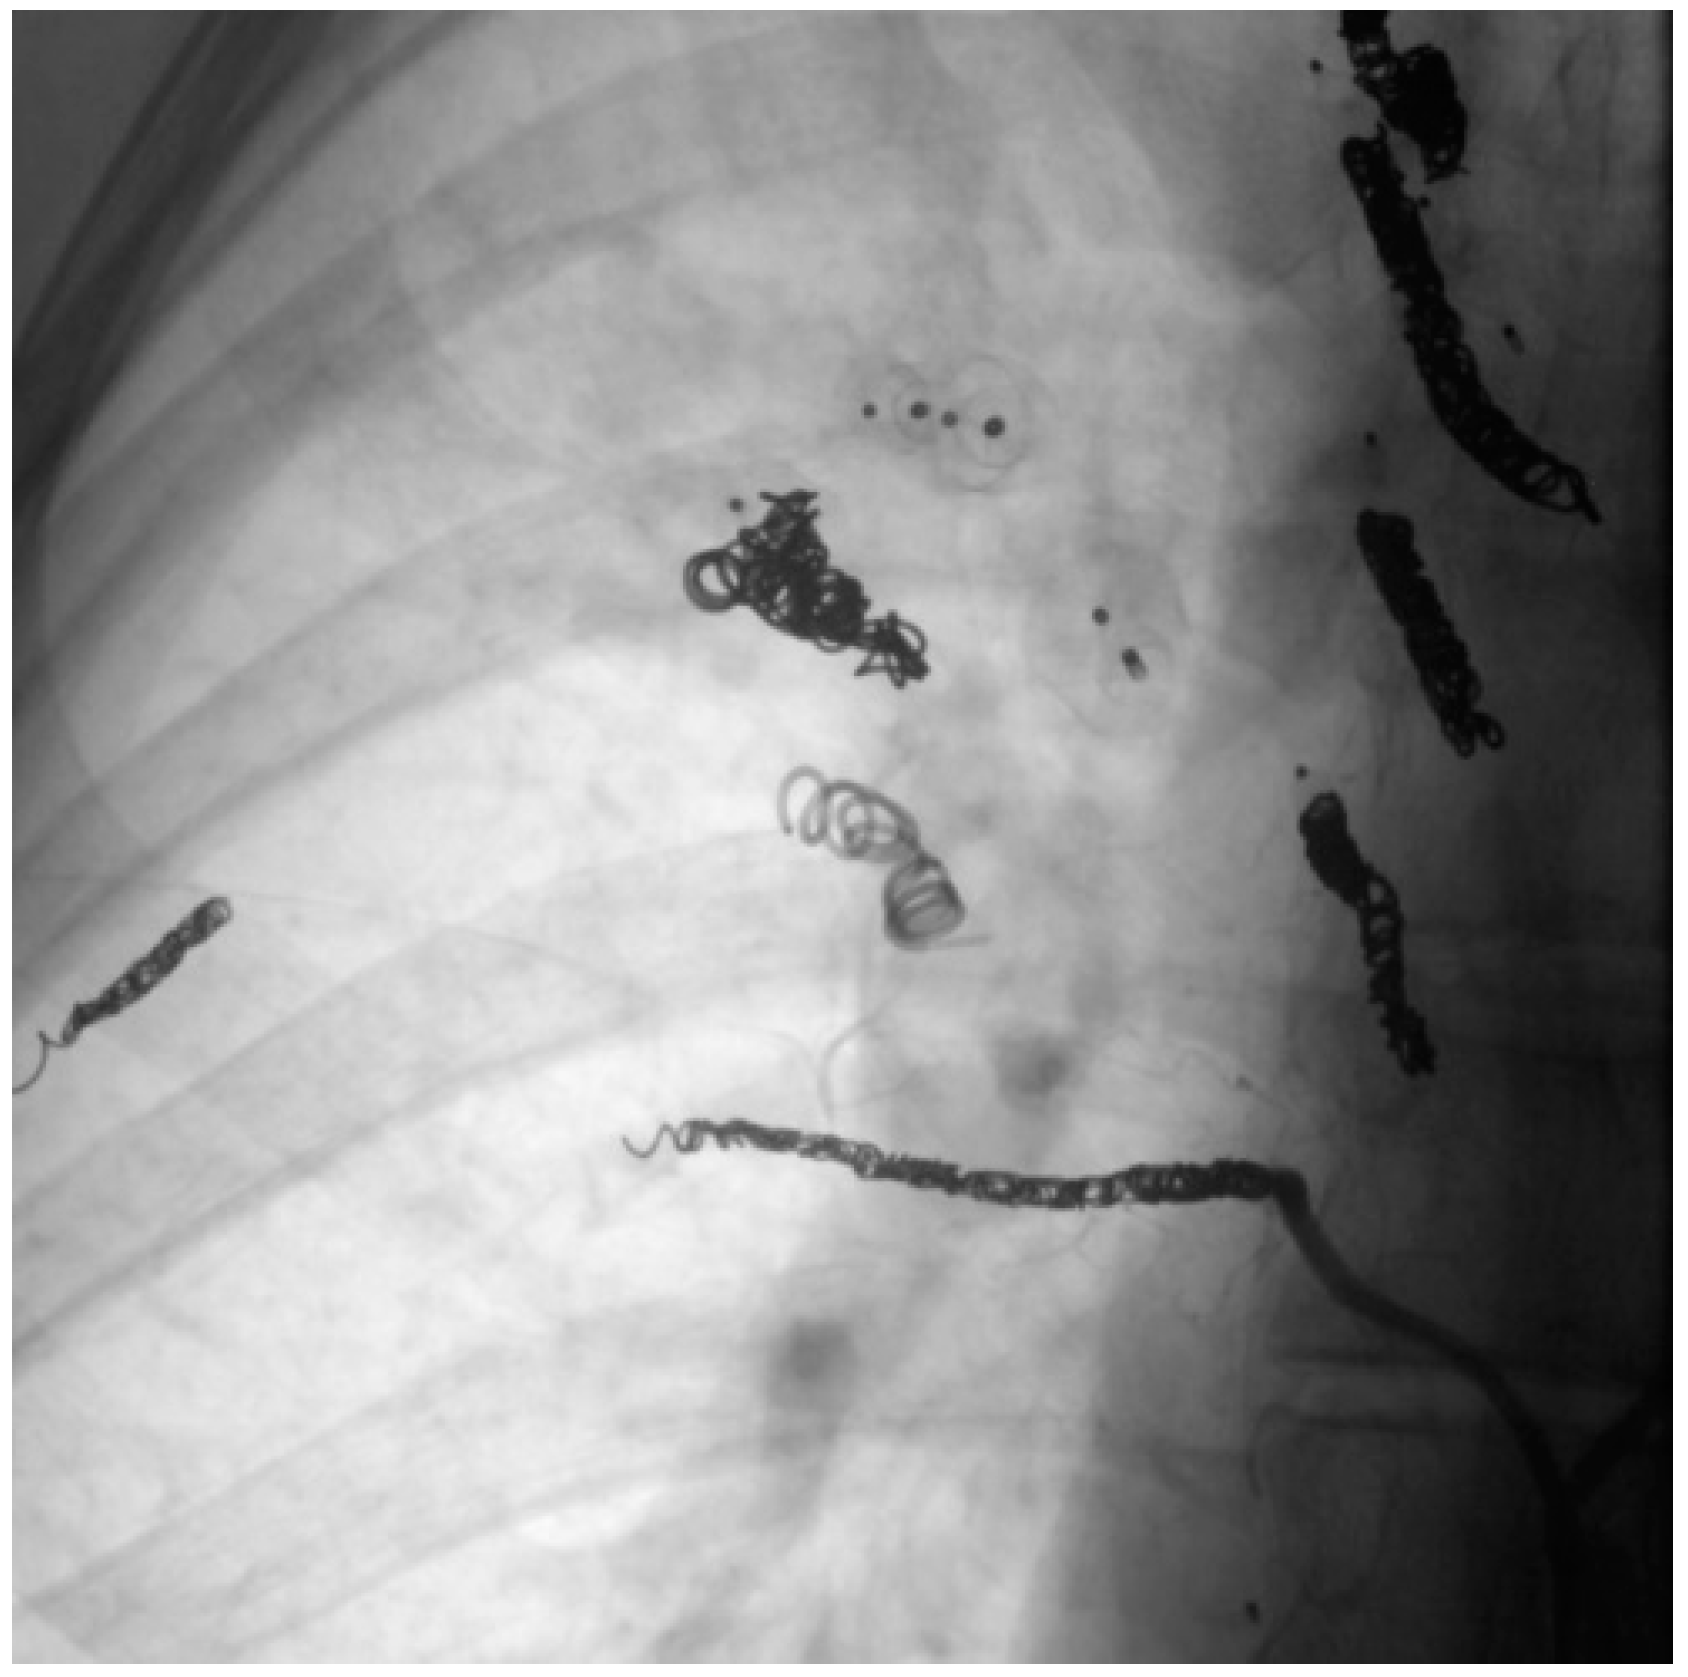

When assessing the implanted embolization material, it was also noticed that some of the coils in the DSA appeared thinner than others. Figure 11 shows a Nester® Embolization Coil from Cook Medical, which is available in a thickness of 0.035 inch and is regularly used in our department. In ten patients with a total of 29 recanalized AV shunts, the implanted coils appeared thinner than those used at our department, with these accounting for 45.3% of the total number of recanalized AV shunts. An example is therefore shown in Figure 12. In this context, a possible correlation between the use of coils with a lower thickness and a possible increased recanalization rate after embolization was discussed.

Figure 11. Nester® Embolization Coils with a thickness of 0.035 inch.

Figure 12. Coils of a patient with external treatment and which appear thinner than the Nester® Embolization Coil.